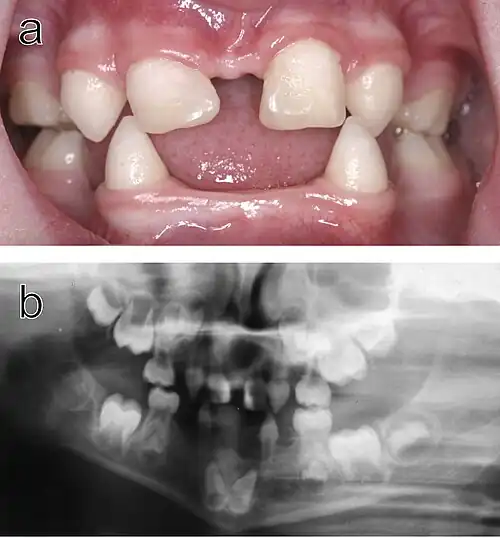

Dental abnormalities in a five-year-old girl from northern Sweden who suffered from various symptoms of autosomal dominant hypohidrotic ectodermal dysplasia (HED) a) Intraoral view. Note that the upper incisors have been restored with composite material to disguise their original conical shape. b) Orthopantomogram showing absence of ten primary and eleven permanent teeth in the jaws of the same individual.

Hypohidrotic ectodermal dysplasia (HED) is the most common subtype of the disease. Clinical cases of patients with this condition display a range of symptoms. The most relevant abnormality of HED is hypohidrosis, the inability to produce sufficient amounts of sweat, which is attributed to missing or dysfunctional sweat glands. This aspect represents a major handicap particularly in the summer, limits the patient's ability to participate in sports as well as his working capacity, and can be especially dangerous in warm climates where affected individuals are at risk of life-threatening hyperthermia. Facial malformations are also related to HED, such as pointed or absent teeth, wrinkled skin around the eyes, a misshaped nose along with scarce and thin hair. Skin problems like eczema are also observed in a number of cases.[11] Most patients carry variants of the X-chromosomal EDA gene.[12] This disease typically affects males more severely because they have only one X chromosome, while in females the second, usually unaffected X chromosome may be sufficient to prevent most symptoms.